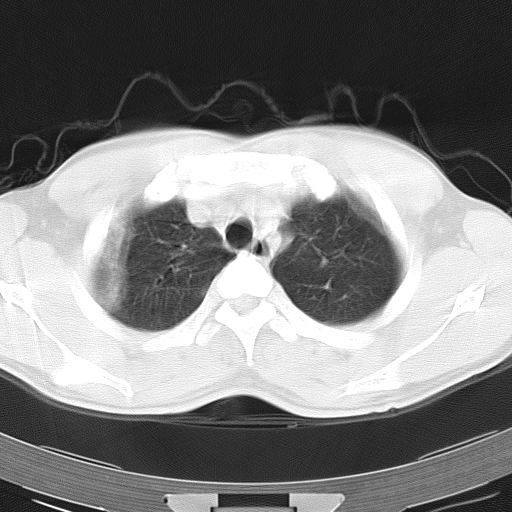

标题: CT12379:男,34岁,肺部病变,请求会诊!

男,34岁,咳嗽2~3个月,无咳血,病初有发热。

两上肺磨玻璃样改变,均位于肺外周,考虑1、肺泡蛋白沉着症?2、肺泡炎?请询问有无养鸟史 3、脱屑性间质性肺炎?建议进一步检查、复查随访

两上肺的ggo,靠近胸膜,不是以节段分布,青年男性,个人意见为吸入性的真菌感染可能为大------------呼吸内科医生

两肺上叶近胸膜磨玻璃样阴影,考虑1、炎性病变。 。2、过敏性炎症?

病灶特点:

分布在肺野的外带,病灶边缘清楚,病灶以磨玻璃影为主夹杂少许纤维状高密度影

支持zhangzhongshou主任,考虑蛋白沉着症可能性大

再仔细阅读该病人的ct片,我们不难发现,病例所表现的正是外围型的肺泡蛋白沉积症表现,即:为多发性条片状、斑片状及斑块状高密度影,弥散、对称或不对称分布于两肺或一侧肺外围部位。病变区与正常肺组织及脏层胸膜面分界清晰,呈地图样改变。